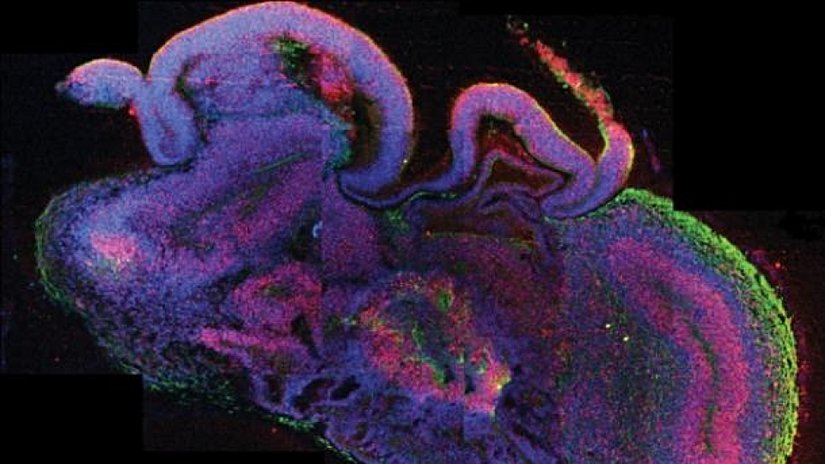

Japon bilim insanları, Stem Cell Reports dergisindeki yayınlarında ciddi sonuçlar bulduklarını belirttiler. İlk kez bir ekip, beyin "organoid"inden, yani organa benzeyen ve onlar gibi faaliyet gösteren çoklu hücre türleri içeren üç boyutlu fonksiyonel yapılardan gelişen nöronların elektriksel aktivitesini kategorize etmeyi başardı. Hazırladıkları beyin organoidinde nöronların kendiliğinden ortaya çıkan, senkronize bir şekilde ateşlenmelerini sağlayan uzun mesafeli bağlantılar kurduklarını bildirdiler.

Nöronlar, sadece uzun mesafeli bağlantılar kurmayıp, bireysel karakteristik aktivitelerini de koruyarak senkronize bir şekilde ateşlendiler. Üstelik ağ gücünü arttıran veya azaltan ilaçlarla tedavi edildiğinde, kültür de tam beklendiği gibi tepki gösterdi.

Ancak bu, kültürün bilinçli olduğu anlamına gelmiyor. Bunun yerine, kültürlenmiş beyin organoidindeki nöronların, hafızanın oluşumuna benzer bir şekilde kendiliğinden elektriksel modeller geliştirme kabiliyetine sahip olduğunu göstermektedir.

Ekip, bir miktar kök hücreyi alıp serebral korteksteki yapıya benzeyen -katmanlı bir yapıya sahip olan- bir organoid yetiştirdi. Yaklaşık üç ay sonra Sakaguchi, ekibi ile birlikte hücreleri dokudan aldı ve daha sonra başka bir kaba yerleştirdi, ancak bu kez ayrı ayrı yetiştirildiler. Bunun sonucunda hücreler kendilerini kümeler halinde organize etmeye ve yakındaki diğer kümelerle ağlar oluşturmaya başladılar.

Ekip, nöronların inanılmaz derecede sağlıklı olduğunu fark etti. Geleneksel beyin organoidi kültürlerinden çok daha uzun, bir yıl boyunca canlı tutulabiliyorlardı. Bazı nöronlar, komşu nöronların aktivitesini hızlandıran kimyasalları dışarı pompaladıkları için eksitatör (uyarıcı) hale geldiler; diğerleri de komşu nöronların ateşlenmesini bastırdığı için inhibitör (engelleyici) oldu.

Sofistike genomik ve moleküler analizler yoluyla bilim insanları; bu nöronların nihayetinde kortekse özgü "katmanlı pasta" benzeri bir yapı geliştirdiklerini ve ikinci trimester fetusla aynı nöron kastını meydana getirdiklerini gösterdiler.